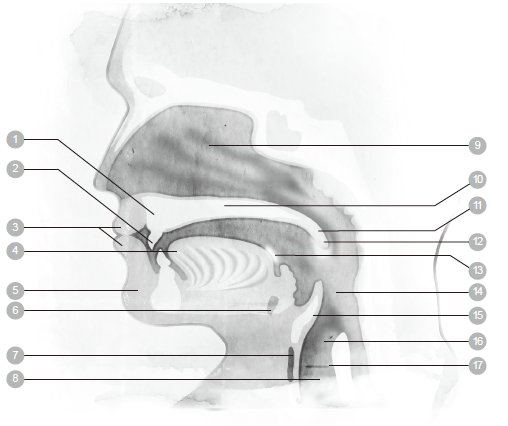

◆鼻子和嘴巴

我们所呼吸的空气是从鼻子和嘴巴进入体内。嘴巴比鼻子更能吸入大量的空气,原因在于嘴巴的空间比鼻腔的通道更大。人们说话、唱歌、吹奏管乐器或是做动作的时候,或许会需要用嘴巴来呼吸。

以嘴呼吸时,空气受到的阻力比较小,因此可以快速进入肺脏。不过,用鼻子呼吸的话,空气是温暖湿润的,而且会受到过滤,对健康有好处。无论以嘴或鼻子呼吸,空气都是经过喉咙的后方,接着再经过气管,继续往下流动。气管进一步分叉成支气管,把空气带进肺脏。

进食的时候,食物和饮料是经过食道而进入胃部,食道位于气管后方。会厌是一小块扁平的软骨,吞咽的时候,会厌会封闭气管,于是食物和饮料被引入胃部,如此便可防止食物经由气管而进入肺脏。

呼吸和吞咽的动作无法同时间进行,这就是为什么当我们吃饭吃得太急,或是一边吃饭一边说话,食物偶尔会跑错了地方。

◆气管

气管是一根大约十公分长的管子,直径不到二.五公分。气管开口位于喉头下方,往下延伸到胸骨的后面。气管是由具有弹性的软骨所构成,不过非常强韧,因为它必须一直保持开放的状态。气管分叉成两根小一点的管子,称为支气管。两边的肺各有一根支气管。

1 鼻子 6 肋间肌 11 气管

2 口 7 横膈膜 12 肺

3 会厌 8 鼻腔 13 支气管

4 胸膜 9 咽头(喉咙) 14 肺泡

5 肋骨 10 喉头

◆支气管

支气管是深入肺脏的主要通道,空气会从喉头进入支气管。支气管有两个分支,空气可以进入左边的支气管,也可以进入右边的。

支气管一再分叉开来,如同一棵树的树枝一样。越接近肺脏的支气管分叉得越细小,最终变成细支气管。接着,这些通道变形成微小的气囊,称为肺泡,肺泡便是空气和二氧化碳进行交换的地方。